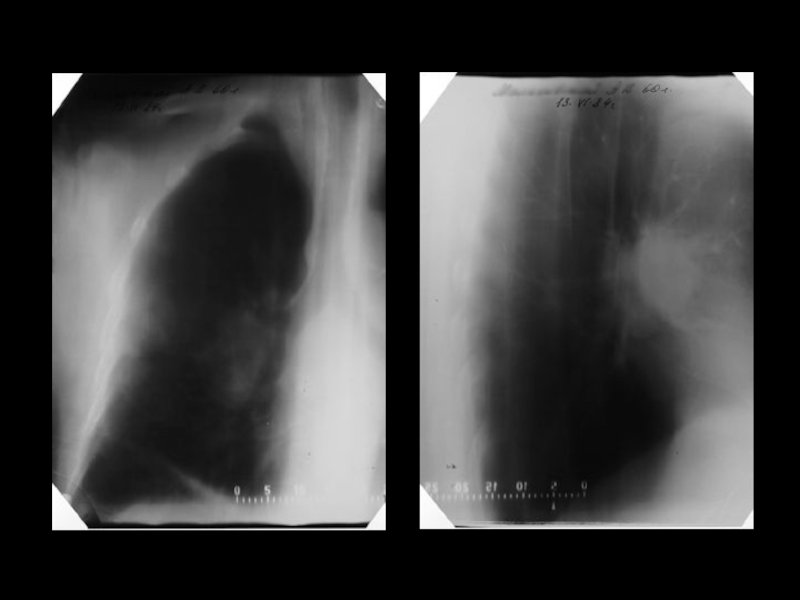

Центральный рак легкого

ЛУЧЕВАЯ ДИАГНОСТИКА РАКА ЛЕГКОГО

АКТУАЛЬНЫЕ ВОПРОСЫ РЕНТГЕНОЛОГИИЦентральный рак легкогоЛУЧЕВАЯ ДИАГНОСТИКА РАКА ЛЕГКОГО